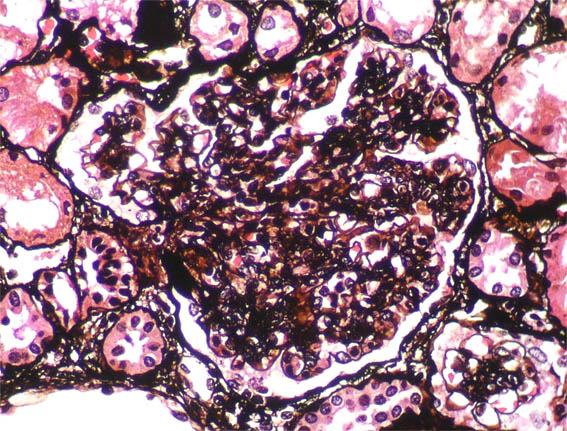

Figura 5.

Plata-metenamina, X400.